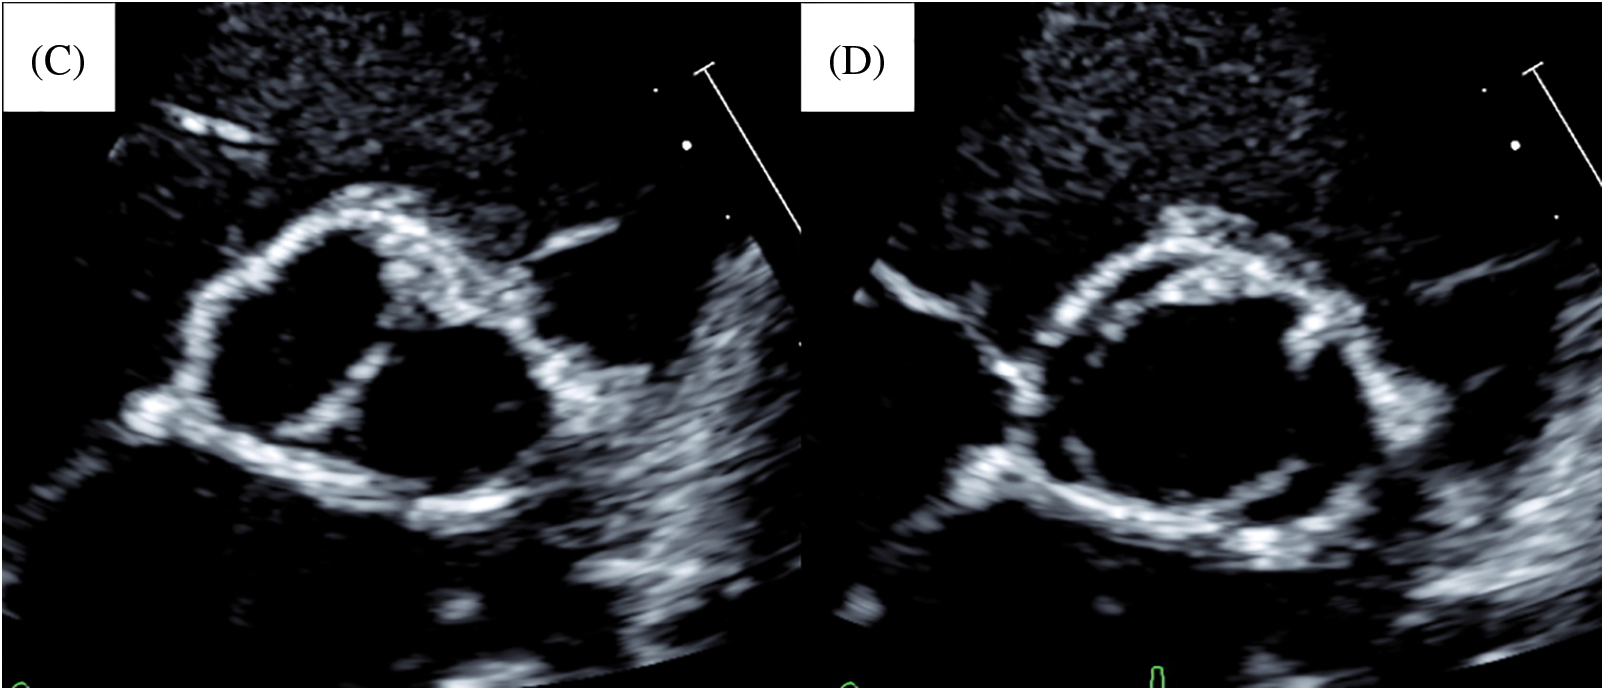

Simultaneously, the left and right cusps were divided at the anterior commissure. Both cusps were sliced to improve mobilization. We performed bicuspidization by commissuroplasty [3] using glutaraldehyde-treated (3 min) autologous pericardium (Figs. 2 and 3). The commissure was made along the longitudinal aortotomy site. Concomitantly, we performed coronary ostium augmentation of the left coronary artery. The cardiopulmonary bypass and cardiac arrest times were 157 and 87 min, respectively. Postoperatively, no AR was observed, and the peak velocity through the aortic valve was 1.9 m/s (Figs. 4A and 4B). A follow-up at 8 years postoperatively (Figs. 4C and 4D) revealed mild AR and a peak velocity of 3.9 m/s with mean pressure gradient of 35.9 mmHg. In addition, the end-diastolic posterior wall thickness was 6.49 mm (113% of normal, Z score = 1.7), which suggested left ventricular hypertrophy. He had no signs of heart failure. His aortic annular diameter increased along the normal annular diameter (Fig. 5), with a recent aortic annular diameter of 15.9 mm (113% of normal, Z score = 2.1).

Figure 4: Postoperative and last follow-up echocardiogram of case 1. (A) Postoperative image in diastolic phase. (B) Postoperative image in systolic phase. (C) Last follow-up image in diastolic phase. (D) Last follow-up image in systolic phase